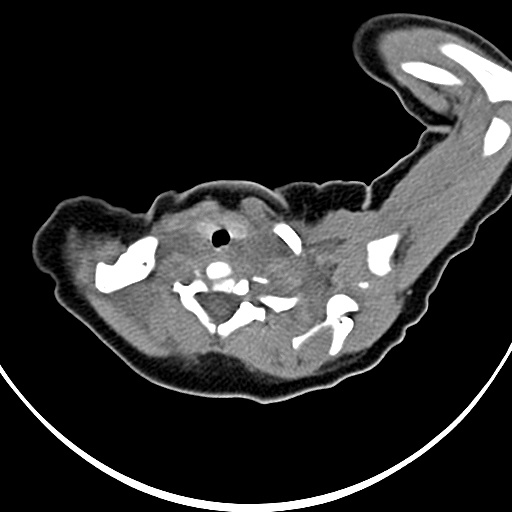

标题: PED1779:左侧锁骨下方异常密度影 请指教 [打印本页]

患者,男,1月,出生后一月,无明显诱因出现颈部左前方肿块。体检:左侧颈部轻度凸起包块,触之较硬。

病灶与左侧胸锁乳突肌分界不清,软组织密度,不似囊性改变,从病人的年龄及病变性状首先要除外先天性斜颈(肌性斜颈)可能。

左侧胸锁乳突肌肿大,考虑产伤所致

胸锁乳突肌挛缩(斜颈)?